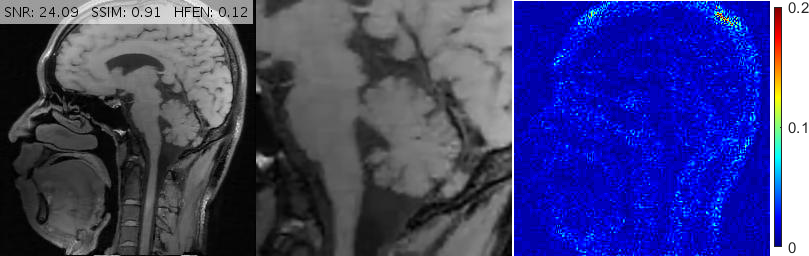

Fig. 13 demonstrates various reconstructions for an axial -weighted brain image under a 20% Cartesian sampling. The magnified views show that FDLCP has smoothed out fine cerebral details while DAMP, ADMM Net, GBRWT, pFISTA, TL and TGV+Sh have introduced severe artifacts into the image, not least among them is a very large dark hole in the parietal lobe. BM3D provides a better result but this method also degrades the ventricles. The proposed framework again gives the best result with the cleanest error map.

For convenience, in Figs. 10, 11 and 13 we have inserted the SNR, SSIM and HFEN values for each method to the top of the corresponding reconstructed image. Moreover, some reconstruction errors in compared methods and their corrections in the proposed method are annotated with arrows.